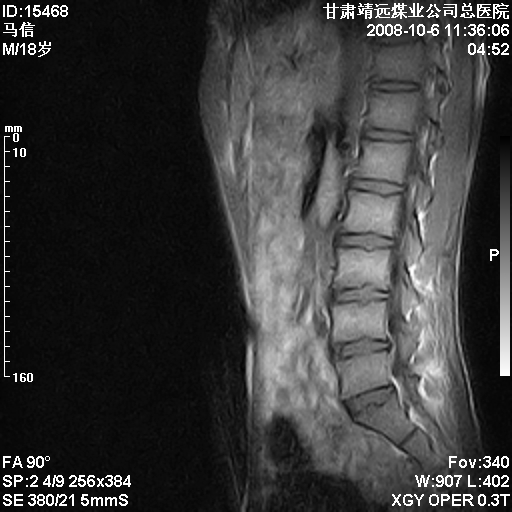

患者18岁,学生,在玩耍中受伤来检查,患者喜欢打篮球。颈椎内异常信号影,我们考虑占位,但是不像占位,又考虑硬膜囊的增厚,大家关建看颈椎椎管内的那个异常占位信号

腰椎的改变是不是正常发育的改变,还是打篮球的长期慢性损伤。

考虑 c3-4 c4-5 c5-6椎间盘突出,l3-4 l4-5 l5-s1椎间盘变性

颈椎建议做增强扫描;腰椎诸椎终板骨骺炎。

后纵韧带增厚,颈2/3、3/4、4/5、5/6椎间盘变性、突出;椎体有旋转,提示椎小关节有问题;腰椎间盘变性,许莫氏结节。

后纵韧带增厚,颈2/3、3/4、4/5、5/6椎间盘变性、突出;椎体有旋转,提示椎小关节有问题。腰椎诸椎体终板骨骺炎可能性大!支持!